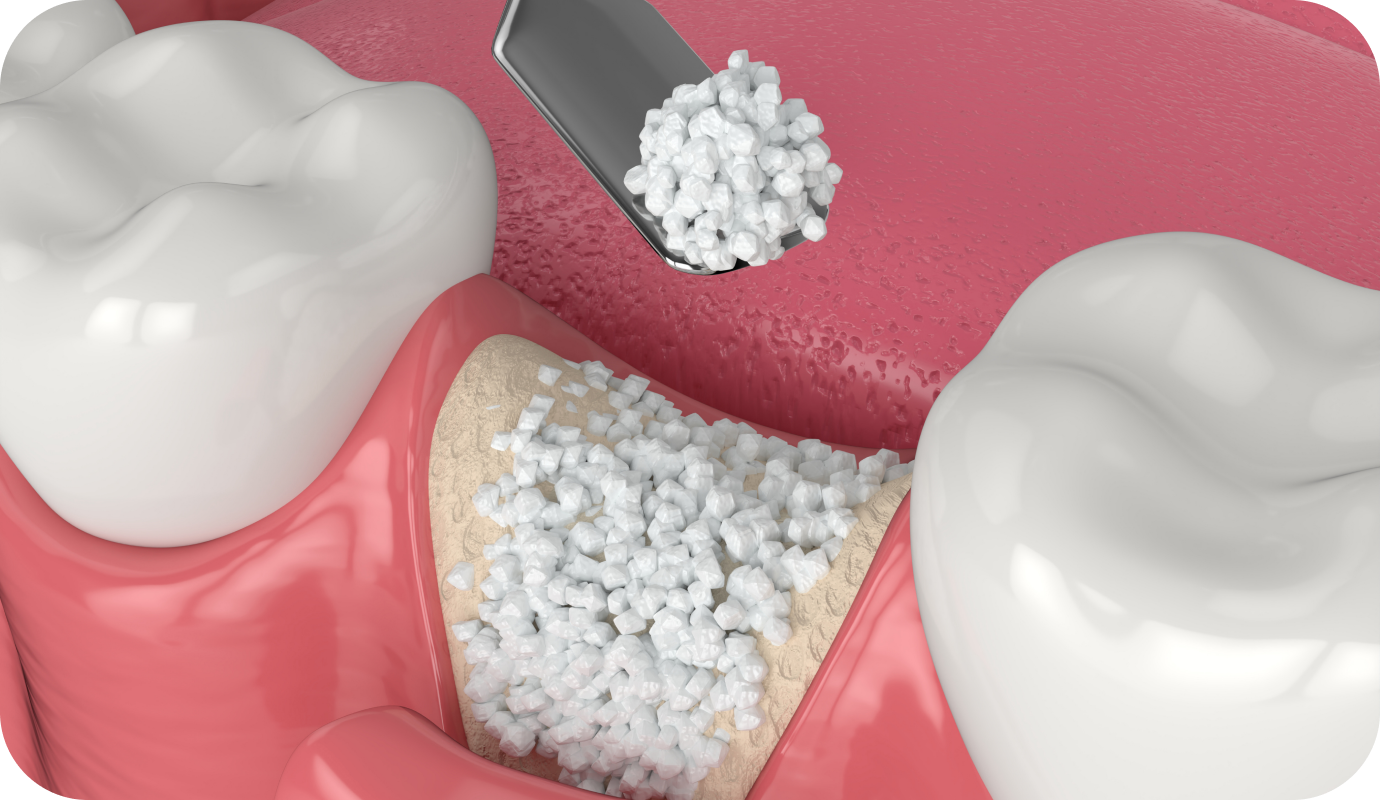

Greffe osseuse

La greffe osseuse est une intervention essentielle pour restaurer le volume osseux de la mâchoire, souvent nécessaire avant la pose d’un implant dentaire. Réalisée au cabinet du Dr Guex, cette procédure permet de renforcer la structure osseuse et de garantir la stabilité des traitements ultérieurs. Découvrez les étapes, les indications, et les recommandations associées à Read More…